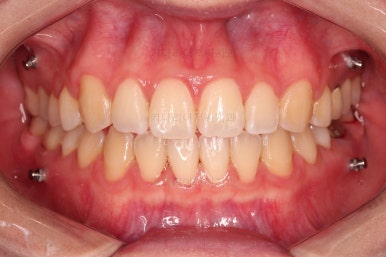

5. 치료의 종료

부산치아교정잘하는곳 키다리아저씨치과에서 치료를 종료했을 때의 사진입니다.

위아랫니가 가지런해졌고요.

다시 틀어지지 말라고 적절한 유지장치를 구성합니다.

보철 치아의 위치/크기로 인해 100% 중앙선은 맞기 힘드나 가장 잘 맞추어 놨고, 앞니의 각도도 매우 좋아졌습니다.

아래 앞니도 단순히 머리 부분만 뒤로 눕힌 것이 아니라 뿌리까지 뒤로 당겨왔고요.

6. 전후 사진 비교

교합, 가지런함, 앞니 각도 모두 좋아졌습니다.